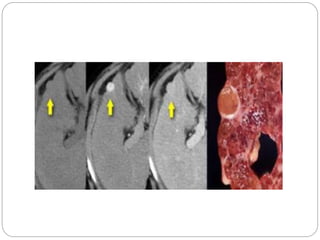

Arterio-portal shunt: The arterial phase CT image shows a

large enhancing lesion (m) in the segments 3 and 4 of liver with

contrast in the left hepatic artery (arrow) and left branch of portal vein

(arrow head) suggesting arterio-portal shunting

Arterial phase  Demonstrationof arterial branches tumour  Arterio portal shunts Arterio-portal shunt: The arterial phase CT image shows a large enhancing lesion (m) in the segments 3 and 4 of liver with contrast in the left hepatic artery (arrow) and left branch of portal vein (arrow head) suggesting arterio-portal shunting